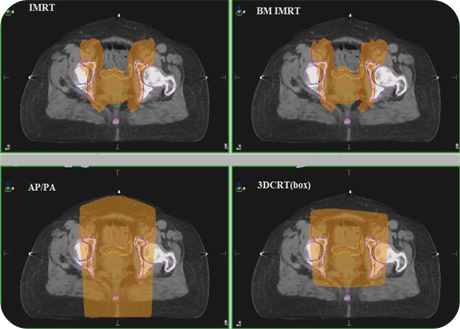

The dose distribution obtained for IMRT, BMS-IMRT, AP/PA and 3DCRT techniques are shown in Figure 1. There were a slightly minor dosimetric differences observed between the four plans in PTV DVHs for all patients individually.

Figure 1, showed that BMS-IMRT does not only reduced the dose to the surrounding risk organs but also limited the dose to the PTV compared with

Figure 1. Colour-wash (95%) showing dose distributions obtained for IMRT, BMS- IMRT, AP/PA and 3DCRT techniques. PTV (red), BM (pink) bladder (yellow), and rectum (green).

3DCRT technique. The AP/PA plans produced sharp fall-off in isodose lines, 3DCRT plans showed better dose coverage to the PTV than AP/PA techniques, however 3DCRT plans showed that there is a greater dose to the PBM.